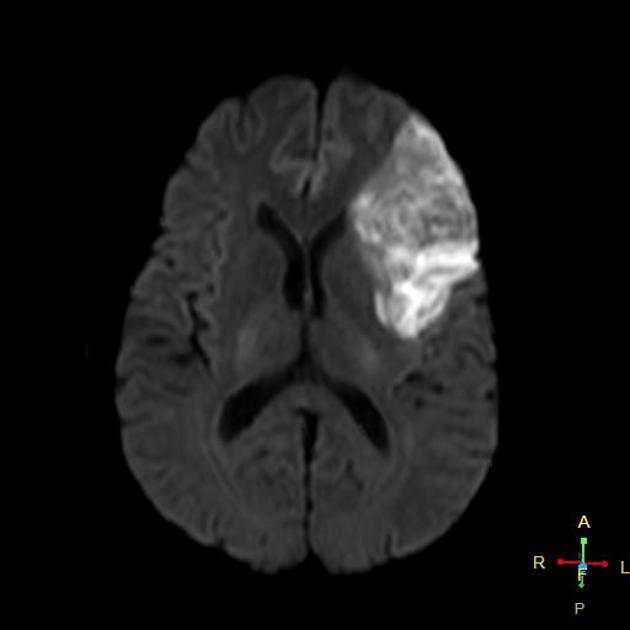

To the left is an MRI Image of a patient suffering a stroke, around what seems like the Left Frontal Lobe. As you can see, the lack of blood flow (Ischemic) creates a whitish, obviously deficient appearance in the brain